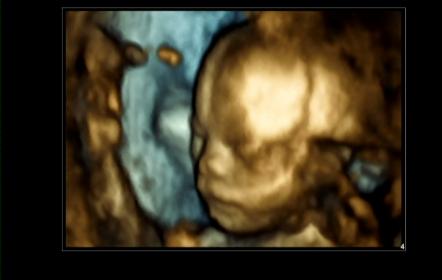

UPDATE!!! Pics included for your confirmation please :)